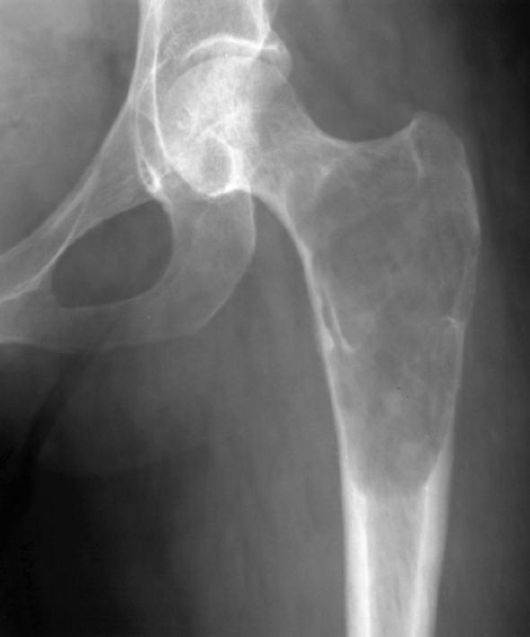

Замечено, что остеосаркома чаще всего развивается в тканях длинных трубчатых костей, к которым относится и бедренная кость. На ее долю выпадает основное количество диагностированных случаев описываемого заболевания – приблизительно в 80% всех диагностированных случаев остеогенных сарком был поражен дистальный конец бедренной кости (тот, который принимает участие в формировании коленного сустава). Такая статистическая закономерность касается всех возрастных групп, у представителей которых было выявлено описываемое заболевание.

На втором месте по поражению – метафиз. Так называют участок кости (в данном случае бедренной), который располагается между ее суставным фрагментом и диафизом (трубчатым участком). Сам же диафиз поражается наиболее редко – у каждого десятого пациента с описываемой патологией.

- рентгенологическое исследование – его информативность не всегда удовлетворяет, но метод позволяет выявить опухоль в месте развития остеосаркомы, а при ее прогрессировании – существенный дефект тканей. К тому же, рентгенологические аппараты имеются даже в небольших клиниках – с их помощью ставят предварительный диагноз, после чего есть смысл направить пациента на прохождение более информативных методов исследования;

- компьютерная томография (КТ) – компьютерные срезы позволяют детально изучить структуру костной ткани в месте поражения;

- хрящевые наросты в области коленного и тазобедренного суставов;